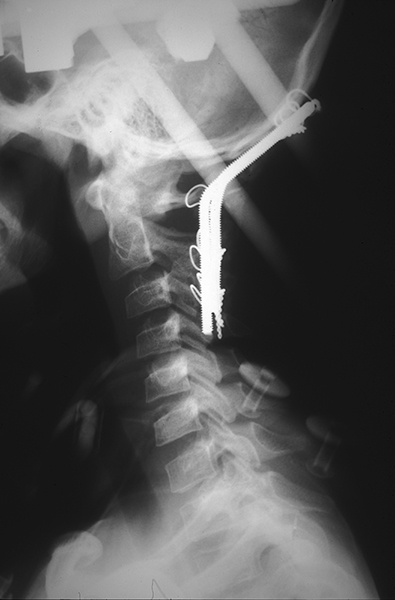

Demonstrating early instrumentation techniques in the emerging field of spinal neurosurgery in the mid 1980s. By the end of the decade, a turf war would break out over who should perform such surgeries, neurosurgeons or orthopedic surgeons.

X-ray of cervical instrumentation.